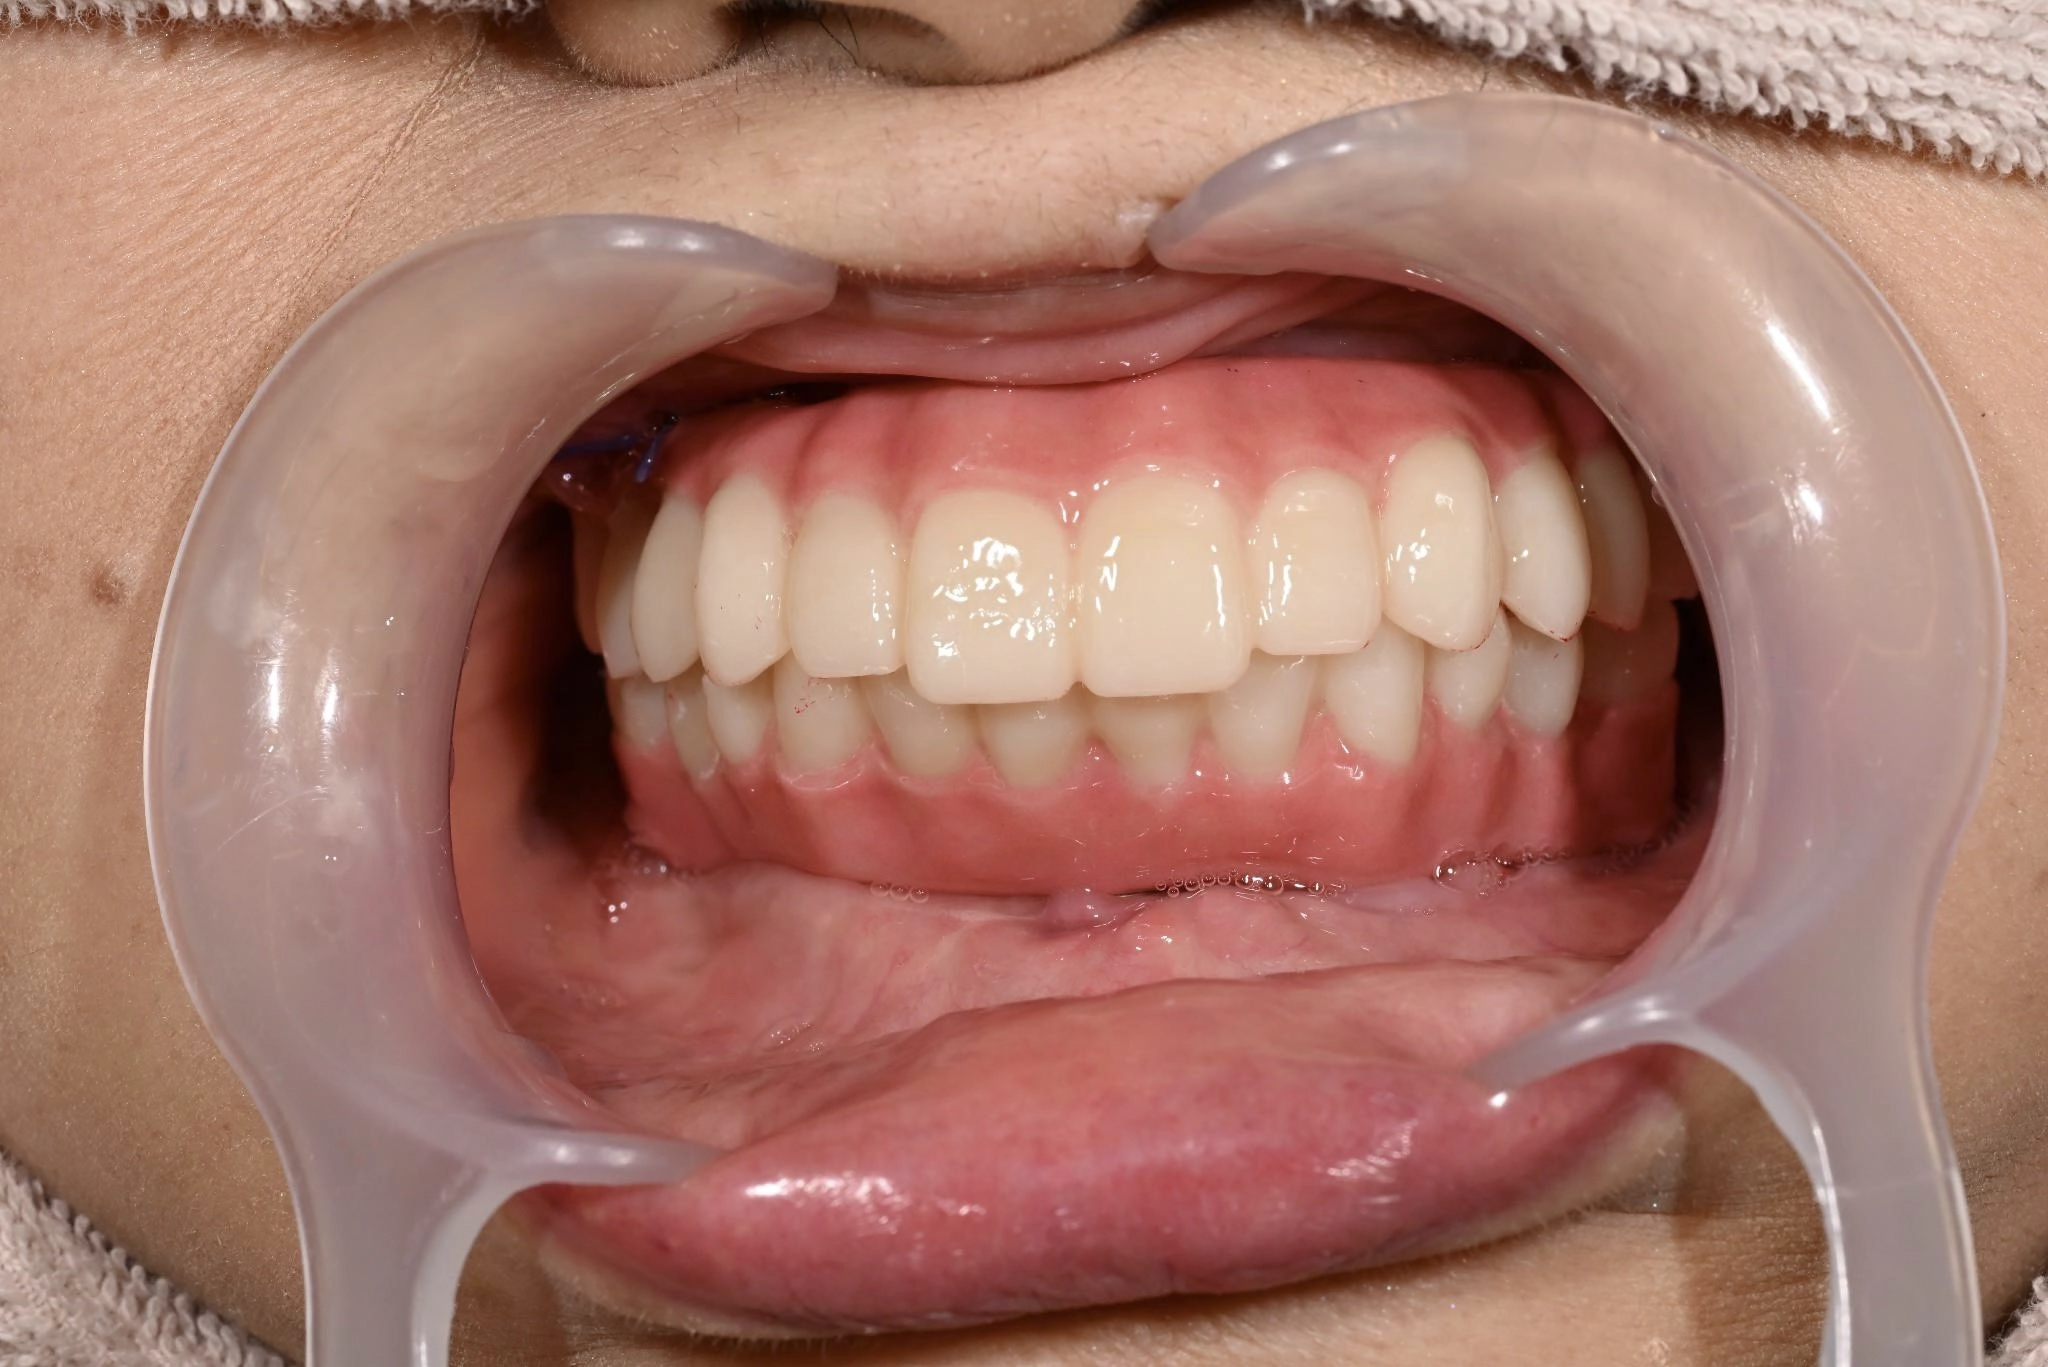

術後

手術前は恐さがありましたが、実際に始まるとあっという間に終わっていました。手術後、入った歯を見たときは綺麗で驚きました。今までの悩みがなくなり、手術をやって良かったと思います。自分と同じような歯の悩みを持つ人に勧めたいです。